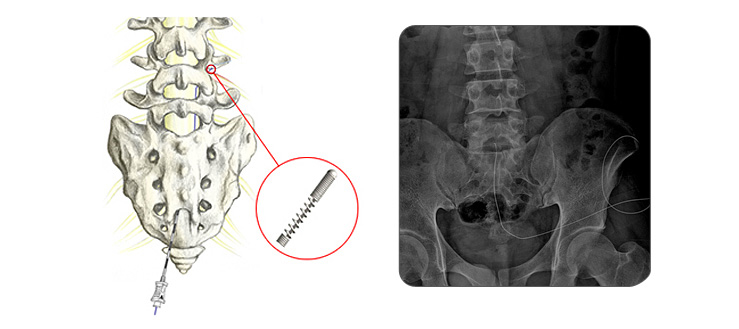

감압적(경막외광) 신경성형술

신경주위 조직의 염증반응이나, 주변 섬유조직의 신경과의 유착은 심한 요통이나 하지방사통을 유발할 수 있습니다. 경막외 신경성형술은 특수고안된 지름 1mm, 길이 40~50cm 정도의 특수 카테터를 통해 통증을 유발하는 신경조직에 도달하여 카테터 끝으로 유착을 풀고, 약물을 통해 유착방지 및 항염증 치료를 시행하는 방법입니다.

치료과정 : - 치료시간은 20분 내외입니다. - 복와위 자세에서 꼬리뼈 근처에 국소마취를 진행합니다. - 꼬리뼈 사이 척추관을 통해 카테터를 삽입하여 병변부위에 위치시킵니다. - 특수 카테터를 통해 유착된 조직을 풀어주고 약물을 삽입합니다. - 특수 카테터를 고정한 후 치료를 마치고, 병실에서 2~3차례 약물을 더 주입하게 됩니다.